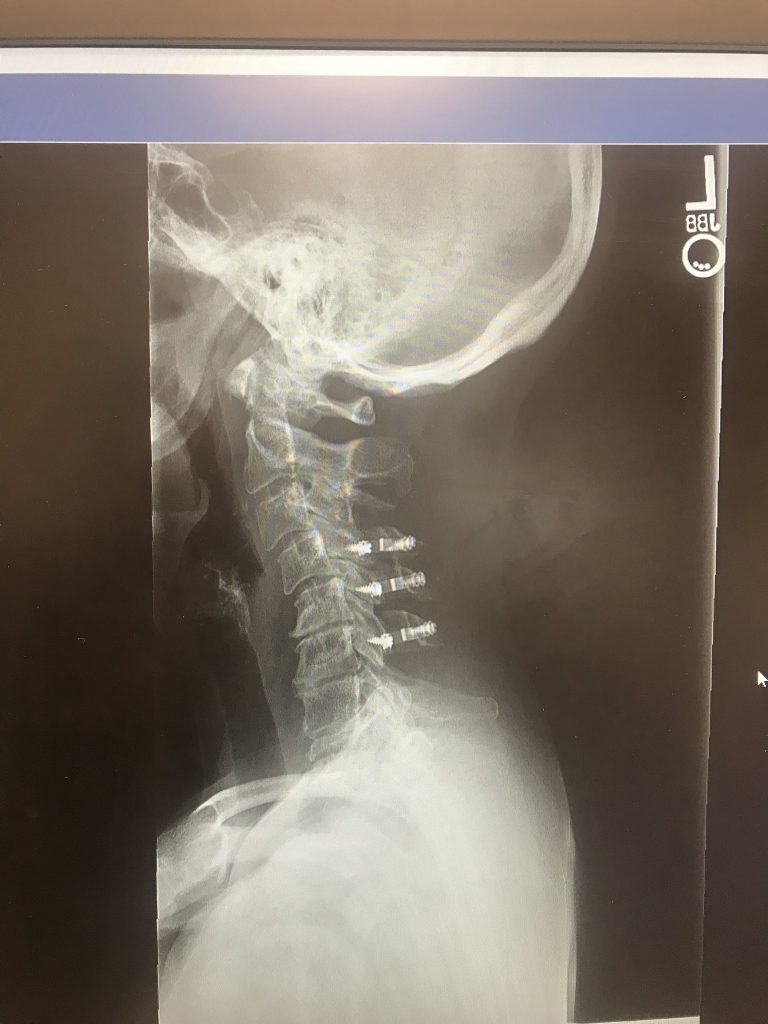

When my right hand became numb and continued with pins and needles, an MRI revealed that I had myelomalacia - a spinal cord injury - and was told that I needed cervical spine surgery. I immediately met with Dr. Han Jo Kim, who made me feel confident that he could stop the progression of this condition with a C3-C7 laminectomy and laminoplasty. I feel so fortunate to have had Dr. Kim as my surgeon as he was able to open up my spinal column and relieve the pressure on my spinal chord by going through the back of my neck and not having to perform a fusion.